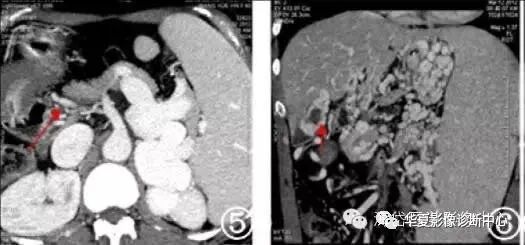

图3 门静脉血栓形成

图4 门静脉主干狭窄闭塞伴侧枝循环建立